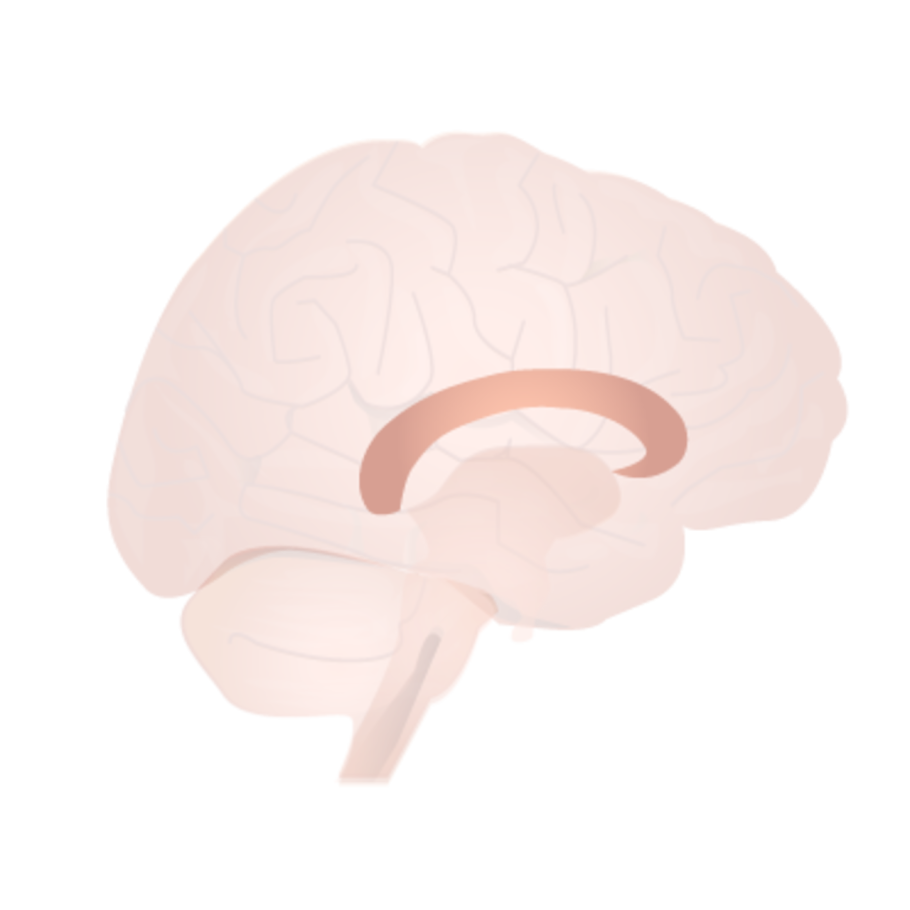

Каллозотомия мозолистого тела

Комиссуральные волокна головного мозга

Мозолистое тело человека